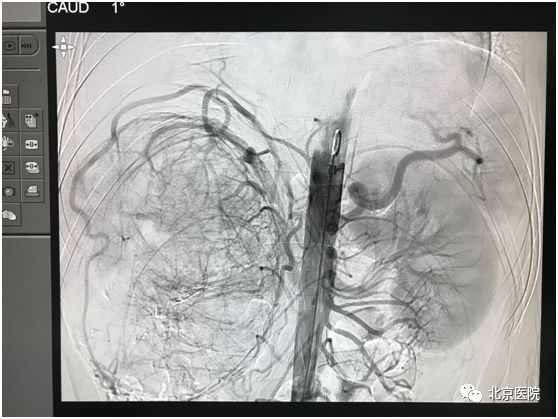

北京医院肿瘤微创治疗中心李晓光团队借助DSA影像技术,经股动脉局麻穿刺置管,利用介入手段对患侧肾动脉选择性造影,证实肿瘤供血动脉、肿瘤生长部位、大小、有无动静脉瘘,再利用超选技术确定目标血管行肾动脉栓塞术。次日该患者如期行“右肾癌根治术”。手术顺利,术中出血量少量,达到预期效果。

肿瘤染色